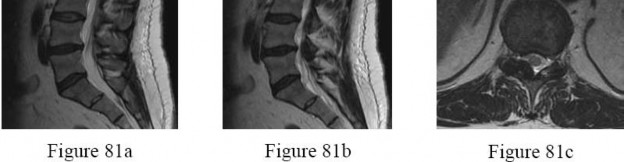

Question 53

A 55-year-old male with known renal cell carcinoma presents with progressive lower extremity weakness and bowel dysfunction.

Imaging reveals a destructive metastatic lesion at L3 causing mechanical collapse and severe canal stenosis. Operative decompression and stabilization are planned. What is the most critical preoperative step?

Explanation